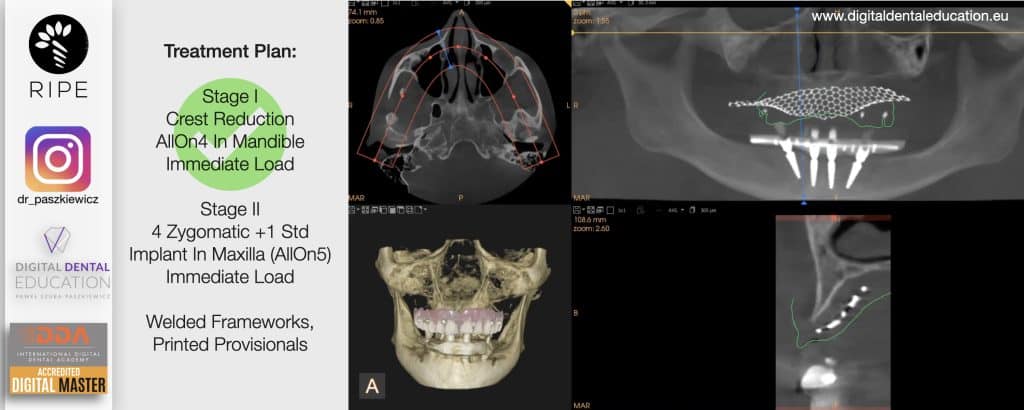

He has invented an AllonX non-impression protocol leading to final restorations post immediate implant full-arch loading, incorporated with desktop scanner (MEDIT) and ModJaw capturing of natural patient’s functional and mastication movements.